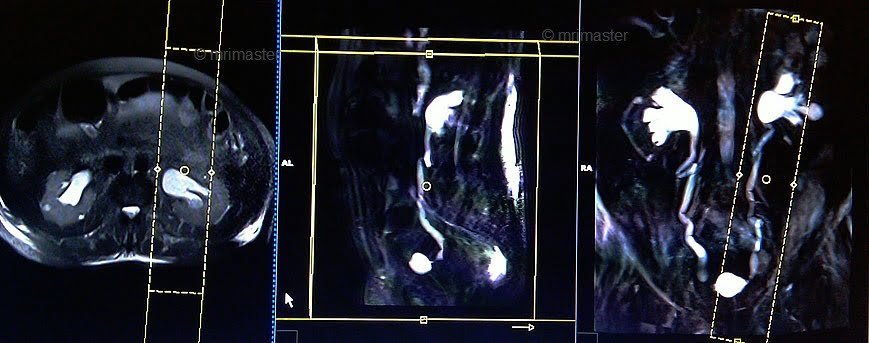

T1 flash FS/ vibe 3D DIXON coronal 2 mm delayed 5 minutes

Plan the coronal slices on the axial plane and angle the positioning block parallel to the right and left kidneys. Check the positioning block in the other two planes. An appropriate angle must be given in the sagittal plane (parallel to the L spine). Ensure that the slices are sufficient to cover the entire urinary system. Use phase oversampling and, in the case of 3D blocks, slice oversample to avoid wrap-around artifacts. The field of view (FOV) must be large enough to cover the kidneys and bladder. Instruct the patient to hold their breath while the images are being acquired.

Parameters

TR 4-5 | TE 2 | FLIP 12 | NEX 1 | SLICE 2 MM | MATRIX 320X320 | FOV 350-400 | PHASE R>L | OVERSAMPLE 50% | IPAT OFF |

T1 flash FS/ vibe 3D DIXON coronal 2mm delayed 10 minutes

TR 4-5 | TE 2 | FLIP 12 | NEX 1 | SLICE 2 MM | MATRIX 320X256 | FOV 350-400 | PHASE R>L | OVERSAMPLE 50% | IPAT OFF |